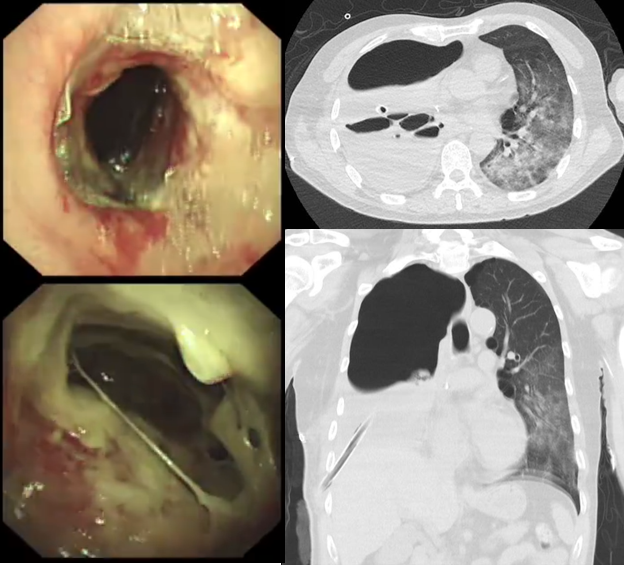

病例459岁男性患者,因“确诊右肺肝样腺癌2月余,气促2天”入院诊断:右肺肝样腺癌并双侧肺门及纵隔多发淋巴结转移住院第3天突发大咯血窒息。紧急插管予呼吸机支持后,床边纤支镜发现气管下段、右主支气管血凝块堵塞,右中、下肺新生物及血凝块导致管腔狭窄(图7)。予纤支镜下药物治疗+射频消融术+钳检等综合介入处理,历经约5小时抢救后生命体征稳定,转介入室行支气管动脉栓塞术,最终成功控制出血,患者病情逐步稳定。

图片

6  患者胸部CT

7  镜下见血凝块及新生物堵塞